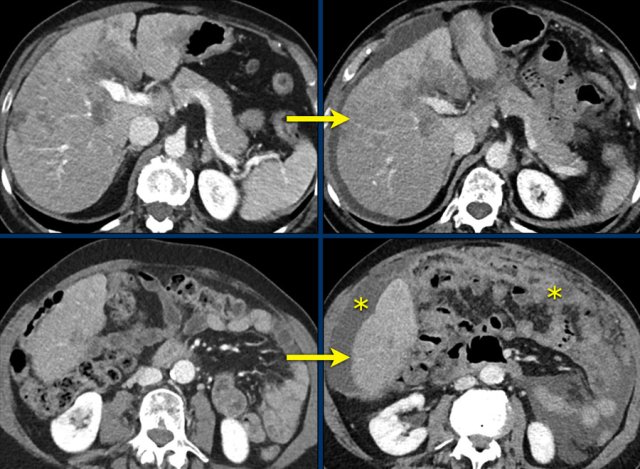

CT images in a 71-year-old female with endometrial cancer with lung, lymph node and peritoneal metastases. Baseline images on the left and images at the first response evaluation during treatment with chemotherapy on the right.

Target lesions:

1. Lung lesion: 26 mm > 31 mm

2. Lung lesion: 35 mm > 38 mm

3. Lymph node carinal: 23 mm > 24 mm

4. Peritoneal lesion: 31 mm > 37 mm

5. Peritoneal lesion: 23 mm > 27 mm

Non-target lesions:

• Other lung lesions: slightly increased

• Other mediastinal lymph nodes: slightly increased

• Other peritoneal lesion: slightly increased

New lesions:

• No

Baseline SLD = 138

Follow-up SLD = 157

Percentage increase from baseline/nadir is 14%, which means that this is stable disease (SD).